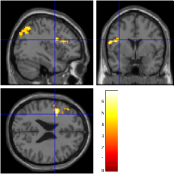

Once the reduced FOV images are available, the proposed pMRI 4D-UWR-SENSE algorithm and its early UWR-SENSE version have been utilized in a final step to reconstruct the full FOV EPI images and compared to the mSENSE Siemens solution. For the wavelet-based regularization, dyadic Symmlet orthonormal wavelet bases [48] associated with filters of length 8 have been used over resolution levels. The reconstructed EPI images then enter in our fMRI study in order to measure the impact of the reconstruction method choice on brain activity detection. Note also that the proposed reconstruction algorithm requires the estimation of the coil sensitivity maps (matrix in Eq. (2)). As proposed in [4], the latter were estimated by dividing the coil-specific images by the module of the Sum Of Squares (SOS) images, which are computed from the specific acquisition of the -space centre (24 lines) before the scans. The same sensitivity map estimation is then used for all the compared methods. Fig. 5 compares the two pMRI reconstruction algorithms to illustrate on axial, coronal and sagittal EPI slices how the mSENSE reconstruction artifacts have been removed using the 4D-UWR-SENSE approach. Reconstructed mSENSE images actually present large artifacts located both at the centre and boundaries of the brain in sensory and cognitive regions (temporal lobes, frontal and motor cortices, …). This results in SNR loss and thus may have a dramatic impact for activation detection in these brain regions. Note that these conclusions are reproducible across subjects although the artifacts may appear on different slices (see red circles in Fig. 5). One can also notice that some residual artifacts still exist in the reconstructed images with our pipeline especially for . Such strong artifacts are only attenuated and not fully removed because of the high level of information loss at .

| mSENSE | 4D-UWR-SENSE | ||

| Axial |  |

|

|

| Coronal | |||

| Sagittal | |||

| Axial |  |

|

|

| Coronal | |||

| Sagittal |